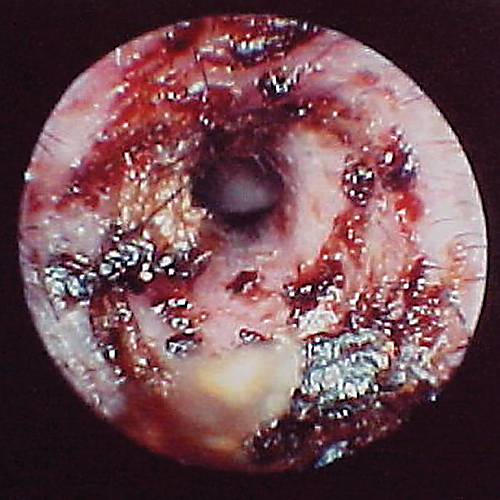

Because the normal pars tensa is translucent, the bulla cavity can be seen when enough light (using a video otoscope) transilluminates the bulla. In otitis media, fluid, if present, can be seen behind the eardrum in the form of bubbles, blood, serum, or pus. Increasing pressure from exudate accumulation can cause the pars tensa to bulge outward. Both of these conditions result in marked pain; pressure must be relieved by myringotomy. Any tissue mass in the middle ear will obscure the ability to view the middle ear (Figure 15). Occasionally, in cats, a middle ear polyp can be seen through the eardrum as a fleshy mass in the bulla.

Otoscopic image of pink mass with red striping seen behind ear drum.

FIGURE 15

Tissue mass behind the eardrum. Note the malleus bone in the pars tensa, indicating the mass is behind the eardrum.

The eardrum may be opaque from chronic inflammation and thickening and/or hyperkeratosis. If the eardrum is opaque, the middle ear cannot be evaluated visually from the ear canal.

In some dogs, the pars flaccida of the eardrum may be bulging from fluid pressure in the middle ear behind it (Figure 16) and may obscure visualization of the pars tensa. Some have suggested that this enlargement may be caused by degranulation of mast cells and resultant edema from atopic dermatitis.7,8 This condition is frequently mistaken for a mass in the external canal and should be closely evaluated.

Otoscopic image of domed eardrum with hair and yellow exudate visible in internal ear canal.

FIGURE 16

Bulging eardrum caused by increased fluid pressure in the middle ear